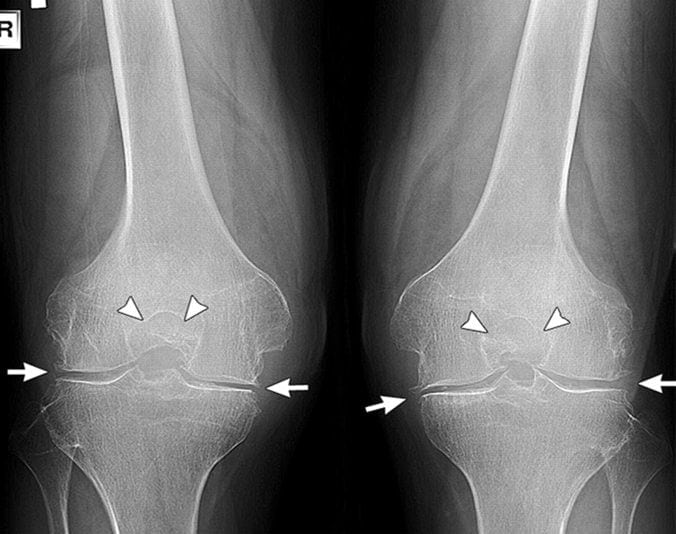

- Гонартроз 1 степени характеризуется повышенной утомляемостью конечности. Кость на этом этапе не претерпевает значительных изменений, однако, едва заметное ограничение движения все же присутствует. Эта степень также характеризуется некоторым сужением суставной щели, которое можно увидеть только на рентгеновском снимке.

- Гонартроз 2 степени сопровождается болевыми ощущениями после нагрузки сустава: во время ходьбы больной слышит хруст в колене. Он не может согнуть или разогнуть сустав полностью. Боль может наблюдаться перед началом движения (стартовая). На снимке заметно сплющивание краев костей.

- Гонартроз 3 степени характерен сильной болью, которая чувствуется, даже если человек находится в состоянии покоя. В пораженной области может возникать отек и повышаться температура. Сустав становится нестабильным, может резко заклинивать.

- Рентгенографию сустава. Тут можно увидеть степень сужения суставной щели, повреждение хряща и кости, наличие скопления солевых отложений, остеофитов.